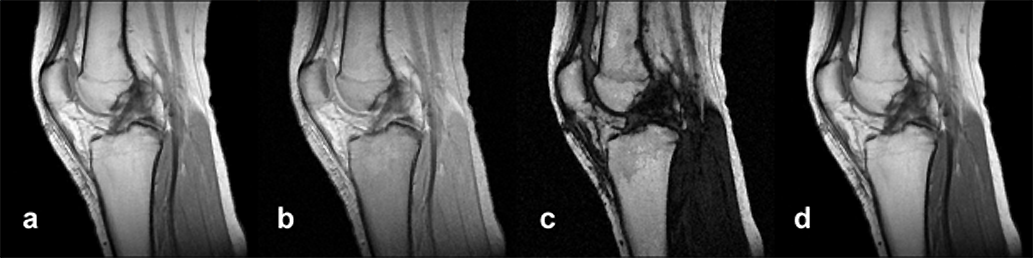

Figura 15-09a:

Simulation of an MR exa­mi­na­tion of a normal knee at 1.5 T. Series of synthetic inversion-recovery ima­ges; parameters TR|TE|TI: (a) 1000|10|20; (b) 1000|10|100; (c) 1000|10|260; (d) 1000|10|500.

Simulation software: MR Image Expert®